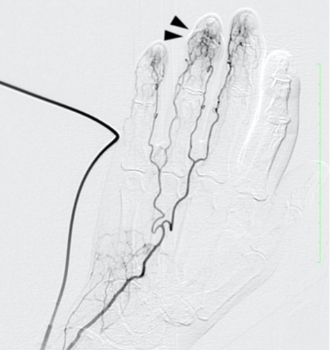

「モヤモヤ血管」とは、慢性的な痛みやこりの原因となる「異常な炎症血管」をわかりやすく表現した呼び方です。血管造影検査で見ると、この血管がモヤモヤとした状態で写っているため、このような名前が付けられました。

動注療法では、エコーを使用して手関節または足関節付近の動脈に細い針を刺し、溶けにくい薬液を注入します。この薬液が「モヤモヤ血管」のみを減らし、痛みを取り除くことを目的としています。

※症例の提供:オクノクリニック様